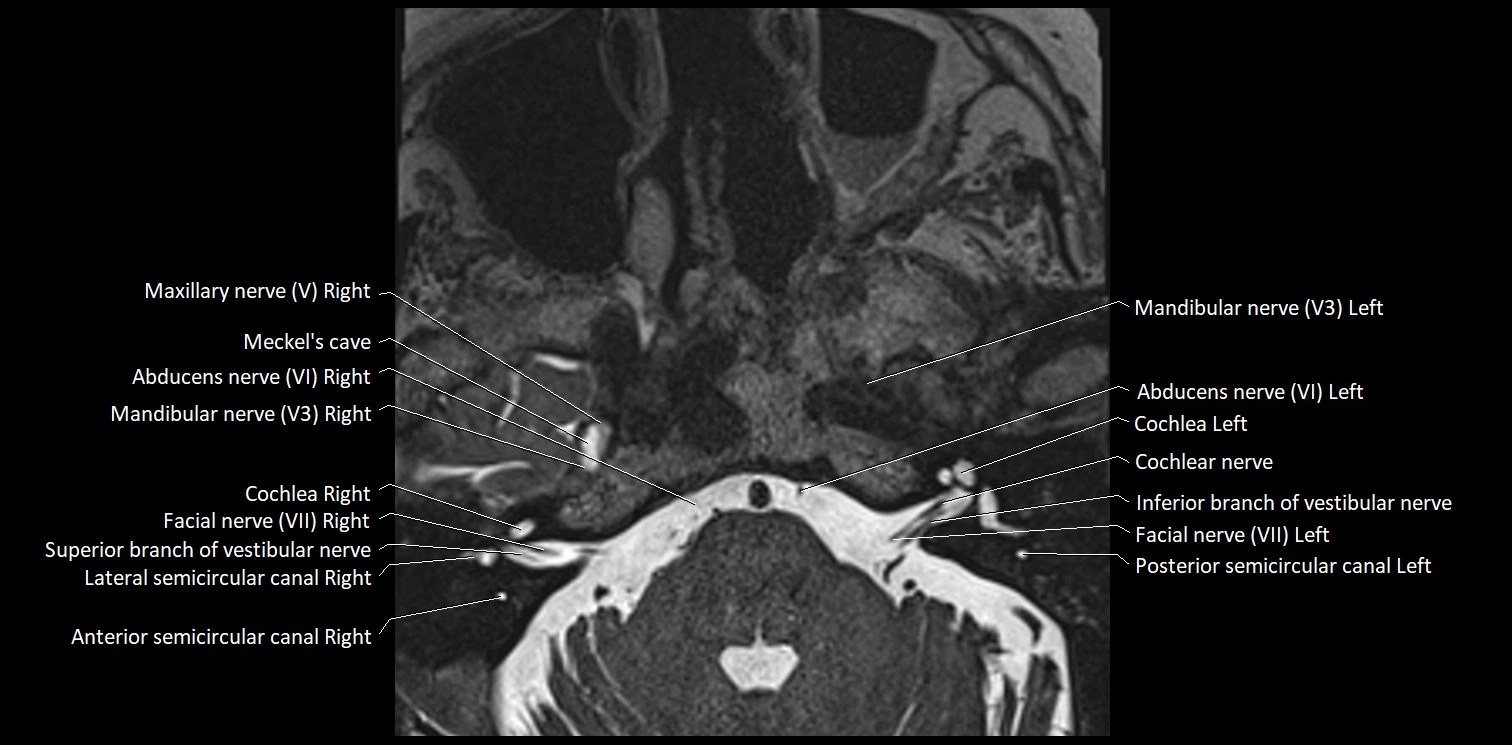

MRI Appearance

• The abducens nerve is a small, thin, linear structure

• Best visualized on high-resolution T2-weighted 3D MRI sequences (e.g., FIESTA or CISS)

• Seen as a hypointense (dark) line running from the brainstem at the pontomedullary junction, traversing the prepontine cistern, and entering Dorello’s canal under the petrosphenoidal ligament, then into the cavernous sinus, and finally the orbit

• May be challenging to visualize in standard MRI due to its small size

• Pathology may be inferred by absence, displacement, or enhancement of the nerve

MRI images

image